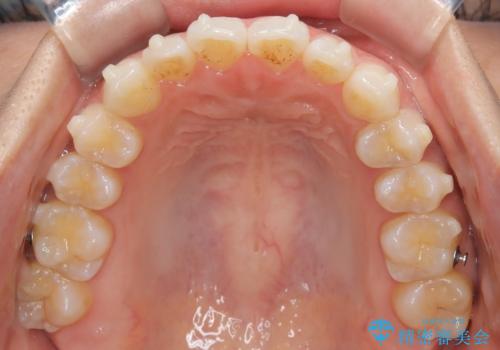

前歯の叢生を非抜歯で改善|インビザライン+IPR・遠心移動・FIX保定

- 前歯部のガタガタ(叢生)を非抜歯で改善するため、インビザラインによるマウスピース矯正を計画しました。抜歯は行わず、歯間をわずかに削るIPR(ディスキング)と奥歯を後方に移動させる遠心移動を併用して、歯を並べるスペースを確保します。歯列が整った後は、FIXリテーナー(固定式保定装置)で後戻りを防止し、安定した歯並びを維持します。

歯を抜きたくないというご希望に応え、インビザラインを用いて非抜歯で歯列を整えました。前歯に必要なスペースを確保するため、歯間をわずかに削るIPRと奥歯を後方に移動する遠心移動を組み合わせました。これにより自然で美しい歯並びを実現。治療終了後は、歯の裏側に目立たないFIXリテーナーを装着し、歯列の後戻りを効果的に防ぎました。患者様は治療中も審美的にストレスなく過ごされ、満足度の高い結果を得られました。